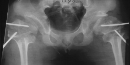

intertrochanteric varus osteotomy was done in 1978 at 11+6 years of age(pre-op

and post-op

- Large iliac wings with small hypoplastic iliac bodies, and poorlyformed

acetabula

- Small capital femoral epiphyses, Dislocation of the hips, Coxa valga